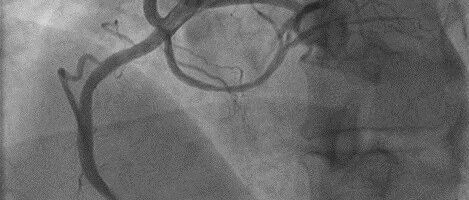

病例 | 年轻患者急性心梗,造影意外发现罕见单支冠脉高位起源于升主动脉,如何权衡介入与解剖结构风险?